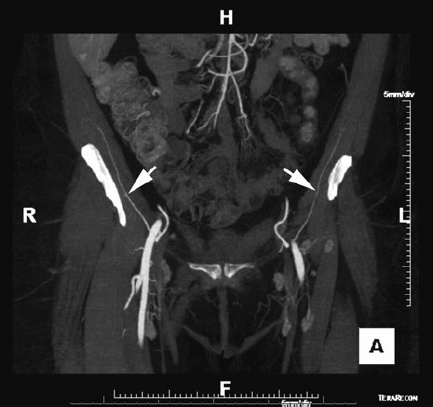

CHAPTER Restoration of the mandible and maxilla are among the most challenging and arduous procedures performed by reconstructive surgeons. Accuracy is paramount to restoring facial appearance and function, including airway maintenance, mastication, swallowing, speech, and, in the case of the maxilla, vision. This chapter focuses on reconstruction of segmental defects of the mandible and maxilla that require grafts and flaps for reconstruction rather than rigid fixation alone. An understanding of the nuances of reconstruction of this region of the body can help the surgeon achieve success in accurate reconstruction and minimize the chances for complications. Because microvascular free flaps play a huge role in contemporary mandibular and maxillary reconstruction, this chapter focuses on avoiding and treating complications related to free tissue transfer in addition to addressing other nonmicrovascular complications that are specific to these structures. Mandibular, and occasionally maxillary, reconstruction with a reconstruction plate that spans a segmental bony mandibular defect was a more popular technique before the development of microvascular free bone flaps. Some centers still rely, at least occasionally, on reconstructive plates when a patient is deemed unsuitable for a prolonged operative procedure involving free tissue transfer or when a surgeon with microvascular expertise is not available. However, experience has shown that such reconstructions are at high risk for complications, including plate fracture and exposure, either intraorally or through the skin of the cheek or chin. To help decrease the rate of exposure, many surgeons have attempted to combine reconstruction plates with a pectoralis major muscle or myocutaneous pedicled flap or a soft tissue free flap. However, Wei et al1 still reported a complication rate of 69% in patients undergoing mandibular reconstruction with a titanium plate and soft tissue free flap in a series of 80 patients. Plate exposure was the most common complication, followed by soft tissue deficiency, deformity of the lateral face, intraoral contracture, trismus, and osteoradionecrosis. Overall, complication rates associated with a reconstructive plate and soft tissue flap are reported to be between 21 and 87%.2 Anterior defects are associated with a higher rate of plate extrusion than lateral defects, as are defects in patients undergoing radiation treatment or with a history of prior irradiation. In addition, larger defects result in significantly higher failure rates than smaller defects. Even when patients are reasonable candidates for a free flap, some surgeons advocate plate or plate and soft tissue flap reconstruction in patients with advanced cancers and a limited life expectancy, because the surgery is usually shorter and recovery is usually faster. However, this approach must be carefully considered on a case-by-case basis, because the incidence of plate-related complications is high. In addition, the results are rarely ideal because of persistent contour deformity and malocclusion. Secondary salvage of such complications with vascularized bone flaps can be performed but tends to be more difficult than if it is performed at the time of the surgical resection. Additional difficulties at the secondary surgery include more challenging dissection of recipient vessels and greater difficulty restoring accurate occlusion because of postoperative and radiation therapy–associated scar contracture. Autologous bone grafts can be used for mandibular and maxillary reconstruction. The bone is revascularized by a process of creeping substitution. Sources of cortical bone graft include iliac crest, split calvarium, and rib. Nonvascularized bone grafts may be used in defects shorter than 5 cm. High failure rates are common in longer segments and in anterior defects. Preoperative or postoperative radiation therapy is usually considered a contraindication for mandibular reconstruction with bone grafts regardless of the size of the defect because of the heavy torque forces on the mandible associated with mastication. Therefore use of nonvascularized bone grafts for mandible reconstruction is usually restricted to patients with benign disease or who require mandibular surgery for posttraumatic or orthognathic rather than oncologic indications. Bone grafts can be used successfully in non–load-bearing parts of the maxilla and midface, such as in orbital reconstruction, but should be supported by well-vascularized tissues, such a pedicled temporalis or free flap, especially in the setting of irradiation. Microvascular free flaps are the preferred method of reconstruction for most segmental mandibular and maxillary oncologic defects. In particular, bone free flaps allow for restoration of facial contour, provide a stable surface for mastication, and, as long as there is adequate bone height and thickness, accommodate osseointegrated implants for dental restoration. Osteocutaneous free flaps not only replace mandibular or maxillary bone, but also are accompanied by a skin paddle that can be used to close soft tissue defects of the oral cavity and/or of the cheek and neck in the case of through-and-through defects. The most commonly used bony or osteocutaneous free flaps include the fibula, iliac crest (deep circumflex iliac artery), scapula, and radial forearm free flaps. Of these, the fibula osseous–osteocutaneous free flap is probably the most commonly used at most reconstructive centers. For specific defects, soft tissue free flap reconstruction alone without a reconstruction plate can give acceptable results for mandibular and maxillary reconstruction. An osteocutaneous free flap is necessary to maintain facial symmetry when there is an anterior defect of the mandible or maxilla.3–6 When there is an isolated posterior defect of the mandible or maxilla, a soft tissue free flap, such as the anterolateral thigh (ALT) or rectus abdominis myocutaneous (RAM) free flaps, can be used if the patient is not a good candidate for an osteocutaneous free flap (because of poor medical condition or peripheral vascular disease, for example).4,5 For the mandible, posterior defects that encompass the condyle, ramus, and as far anterior as the parasymphysis can be reconstructed with a soft tissue free flap. For such defects, the benefits of osteocutaneous free flap reconstruction are arguably less, because the aesthetic appearance is less affected by loss of bony structure, the muscles of mastication cannot generally be reattached in a functional manner, and there is no perfect substitute for the resected temporomandibular joint.7 There will be a tendency for mandibular de viation toward the side of the defect when reconstructed with a soft tissue flap alone that can be mitigated by slightly overcorrecting the volume of the defect with the flap. There is also a tendency toward flap atrophy, especially after radiation therapy, so a bulky flap can help improve the aesthetic result as well. Edentulous patients tend to have more deviation of the mandible, because they do not have teeth to guide their mandible into proper occlusion, which is another factor to consider when opting for a soft tissue free flap over an osteocutaneous free flap in posterior mandible reconstruction. In summary, osteocutaneous free flap reconstruction will tend to have better occlusal outcomes, but bulky soft tissue free flap reconstructions may be acceptable for patients who are not good candidates for an osteocutaneous free flap because of poor functional status, donor site unavailability, or limited life expectancy. For the maxilla, soft tissue free flaps or prosthetic obturators can be considered for defects posterior to the canine tooth.6,8–10 Defects of the posterior hard palate and alveolus can usually be reconstructed with soft tissue free flaps, such as the ALT or RAM free flaps (or the radial forearm fasciocutaneous free flap for obese individuals) with good functional and aesthetic results. It is important to make sure the flap is inset such that it is not ptotic into the oral cavity, because this makes concurrent use of a prosthetic for dental restoration difficult or impossible. For anterior defects, bony reconstruction is necessary to maintain midfacial height, width, and projection.11 Soft tissue free flaps can be combined with titanium mesh or bone grafts to reconstruct the orbital floor when the maxillary defect includes the orbital floor.6 In a review of orbital floor reconstruction for trauma, Kirby et al12 found that autologous bone reconstructions were more likely to be complicated by orbital dystopia and enophthalmos compared with titanium mesh and porous polyethylene, possibly related to increased difficulty in shaping the reconstructed orbital floor, irregular thickness, and unpredictable resorption. Because accurate reconstruction is very important to prevent these complications, as well as decreased vision or even blindness related to excessive pressure on the globe or the optic nerve, the orbit should be preplated with mesh before making osteotomies whenever possible. This mesh can then be used for the reconstruction or serves as a template for reconstruction with bone grafts. Alternatively, I am increasingly using three-dimensionally printed models to guide titanium mesh or bone graft reconstruction (Fig. 52.1). If the orbit is exenterated in combination with a superstructure maxillectomy that spares the alveolus and palate, soft tissue free flaps are usually indicated to obliterate the orbital cavity and close the orbito-sino-nasocutaneous wound.13 If the palate is also resected with the orbit and rest of the maxilla, a multipaddled soft tissue free flap is used to close both the intraoral wound and the orbital wound. Rarely, the defect is so extensive that the orbit and the anterior palate and alveolus are both resected. In such cases, our reconstructive algorithm would call for a soft tissue free flap to fill the orbital cavity and an osteocutaneous free flap to reconstruct the palate and alveolar arch to maintain midfacial projection. Fig. 52.1 A computer-generated model manufactured using three-dimensional printing technology assists the surgeon to reconstruct the left bony orbit by allowing complete visualization of the surgical defect in the absence of soft tissue structures that limit exposure so that hardware or bone grafts can be accurately shaped. Fig. 52.2 A pectoralis major myocutaneous flap used for cheek reconstruction. The flap has contracted inferiorly, causing a large wound dehiscence and, subsequently, a fistula. A palatal obturator is visible through the fistula. The base of the flap is bulky, and neck movement is limited. In patients who are poor candidates for a microvascular free flap reconstruction, the pectoralis major myocutaneous (PMMC) pedicled flap is sometimes used to reconstruct mandibular and maxillary defects.14 Use of this flap, alone or in combination with a titanium plate as described previously, should be considered a secondary option. Functional and aesthetic results are rarely optimal. Complications associated with using this flap include tethering by the proximal flap and vascular pedicle, restriction of neck movement and pulling of the bulk of the flap downward, an unsightly bulge in the neck, and, if adequate cutaneous perforators are not incorporated into the flap design, partial skin-paddle necrosis that can lead to a fistula (Fig. 52.2). If the PMMC flap is used, the skin paddle should be designed so that it is centered over the fourth intercostal space to provide adequate reach, and the proximal flap should be debulked as much as possible15 (Fig. 52.3). A long neck and short torso should be considered a potential contraindication for maxillary and even some mandibular reconstructions because of the inadequate reach of this flap. After major head and neck reconstruction, patients are usually kept sedated and on a ventilator overnight; they are weaned off the ventilator the next morning as tolerated, then transferred to a flap-monitoring floor when they are deemed stable. The advantage of having patients sedated overnight is it prevents unnecessary agitation and vomiting, which may result in an increased risk of hematoma or flap compromise. The disadvantage of keeping patients sedated and on a ventilator overnight is the need for high volumes of intravenous fluids because of the sedation and paralysis. Sedation and paralysis often cause hypotension and require intravenous fluid resuscitation, because vasopressors are generally considered contraindicated after free flap surgery. Therefore patients may become fluid overloaded, which can cause significant cardiopulmonary complications in patients with minimal cardiopulmonary reserve. In recent years, we have opted to allow some patients to breathe spontaneously without ventilator support and avoid sedation after surgery in our institution. These patients seem to recover faster and develop less cardiopulmonary complications with a shorter hospital stay. Venous thromboembolism, infection, and delirium tremens prophylaxis are given as indicated. Fig. 52.3 Maximal length of the pectoralis major myocutaneous flap can be obtained by centering the skin paddle over the interspace between the fourth and fifth ribs, where there are a number of myocutaneous perforators. Bulk in the neck and contracture of the flap can be minimized by making the base of the flap narrow, so that a minimum of muscle is included. Patients routinely receive tracheostomy and nasogastric feeding tube placement at the time of surgery. They then receive tube feedings for 2 weeks, while intraoral incisions are allowed to heal. For uncomplicated intraoral defects, a pureed diet is allowed after 2 weeks if all incisions appear to have healed without a fistula. For more complex defects, such those with a concurrent glossectomy, a modified barium swallow study is obtained to assess swallowing and to rule out a leak in areas that are not easily visualized by physical examination. Tracheostomy decannulation can usually be performed early, around postoperative day 5, when the immediate postoperative swelling has subsided. In select cases of maxillary reconstruction where the flap is not bulky and does not obstruct the airway, a tracheostomy is not performed, but the airway is closely monitored postoperatively in case the flap swells more than expected. Patients who undergo fibula free flap reconstruction are allowed to ambulate as early as postoperative day 2, even in a splint, with weight-bearing as tolerated on the affected limb.16 Early ambulation is important to prevent deep venous thrombosis and pulmonary complications. When not ambulating, the patient is instructed to keep the donor limb elevated at all times, whether in bed or in a chair, to facilitate wound and skin graft healing. We usually allow about 15 to 20 minutes of ambulation or dangling and advance gradually based on the amount of lower extremity swelling observed. When the orbit has been reconstructed, a forced duction test is performed at the end of surgery to rule out entrapment. Corticosteroids are given during surgery and again postoperatively if there is swelling to prevent pressure on the globe. If possible, the patient is woken up immediately after surgery rather than kept sedated so that the vision can be assessed. Visual checks are performed regularly in the postoperative period. Any decrease in vision is an indication for prompt ophthalmologic evaluation. Traumatic optic neuropathy secondary to traction injury is usually treated with high-dose steroids, and any impingement on the optic nerve or pressure on the globe should be relieved by emergent return to the operating room. Diplopia should be followed with computed tomography (CT) to rule out entrapment or suboptimal positioning of grafts and hardware used to reconstruct the orbit. Summary Box Complications Associated with Mandible and Maxilla Reconstruction Microvascular • Flap loss • Pedicle thrombosis • Venous thromboembolism Nonmicrovascular • Infection • Would dehiscence • Fistula Donor Site • Infection • Wound dehiscence • Skin graft loss (flap loss) • Lack of mobility and stability At our institution, trained nursing staff in a dedicated free flap unit perform hourly flap checks for the initial 48 hours and then every 2 hours for the next 48 hours, and finally every 4 hours until discharge. Any concern for a microvascular complication mandates immediate evaluation by a microsurgeon with a low threshold for operative exploration. The use of prophylactic anticoagulants such as heparin, dextran, aspirin, or low-molecular-weight heparin (i.e., enoxaparin) has not been demonstrated to improve flap survival or decrease pedicle thrombosis, and therefore the use of anticoagulants is not routine at our institution except as prophylaxis against venous thromboembolism.16 Signs of flap compromise such as increased swelling and bruising, change in color, or loss of the Doppler signal should prompt an immediate return to the operating room as long as the patient is medically stable. Early intervention remains the single most significant predictor of flap salvage, and, as such, a low threshold should exist for reoperation even at the slightest suspicion for thrombosis.17–19 A negative exploration is far preferable to a lost free flap. Every effort should be made to diagnose the cause of the flap compromise during reoperation (Fig. 52.4). Making the correct diagnosis is critical for salvage and prevention of future thrombotic events. Causes of flap compromise that can be corrected by clot removal and anastomotic revision performed in a timely manner include pedicle compression, kinking, or twisting; focal pedicle injury (e.g., those resulting from intimal injury near the anastomosis); and anastomotic error. Vein grafts are used as needed to replace sections of damaged pedicle or recipient vessel and relieve excess tension on the pedicle and anastomoses. Hypercoagulable conditions may also result in flap compromise and need to be addressed with anticoagulants after thrombectomy and anastomotic revision. Prolonged vasospasm or hypotension resulting in flap compromise are extremely rare and should be considered diagnoses of exclusion. They can be treated with topical vasodilators and by intravascular volume restoration, respectively. More problematic are thromboses related to purulent infection, traction injuries to the perforator(s) or distal pedicle, poor flap design, or injury to the distal circulation during flap harvest. These usually represent unsalvageable conditions. Although anticoagulant and antiplatelet medications are not routinely used as prophylactic agents, I do use them in select cases after a pedicle thrombosis not only if hypercoagulability is suspected but also if we are concerned about a residual clot in the distal microcirculation of the flap that could not be extracted during revision surgery. If return to the operating room is delayed or evidence of thrombosis of the distal flap circulation exists, I also use small doses of thrombolytics, such as tissue plasminogen activator (2–6 mg injected into the recipient artery with a 30-gauge needle or into a vessel side branch while the vein is clamped for several minutes to prevent dilution by release into the systemic circulation).16 However, in general, many of these interventions have not been demonstrated to have a significant impact on flap salvage.17 Fig. 52.5 (a) Computed tomography (axial view) of a right hemimandibulectomy performed for a mandibular ameloblastoma reconstructed with a titanium plate and pectoralis major muscle flap. (b) Intraoral exposure of the titanium plate that occurred several months after surgery. In most circumstances, reviving a free flap requires a lengthy operation, potentially additional donor site morbidity for harvest of vein grafts, added blood loss, need for blood transfusions, and a prolonged hospital stay and recovery. In certain circumstances, consideration should be given to abandoning a flap, immediately or after a judicious salvage attempt, and performing a second reconstruction rather than putting the patient through an extensive flap salvage operation, which may ultimately prove futile. We have demonstrated that delayed flap thromboses occurring later than 3 days after reconstruction and late recognition of flap compromise in which both the artery and vein are thrombosed are associated with significantly lower salvage rates. Similarly, compromised muscle-only flaps are also associated with worse salvage outcomes compared with fasciocutaneous and osteocutaneous free flaps. Multiple attempts at salvaging a failing free flap result in the most dismal prognosis and are not recommended.20 Before every attempt at salvaging a failing free flap, I discuss the possibility of abandoning the flap and performing an alternate reconstruction, either in the same setting or after a delay to wait for more optimal conditions in terms of the patient’s medical condition and the freshness of the surgical team. Ultimately, in the setting of a flap loss, the reconstructive microsurgeon is faced with a dilemma of whether to proceed with another free flap or pursue another option such as a pedicle flap or a prosthetic obturator (in the case of maxillectomy defects).6,21 In my experience, the loss of a free flap does not preclude the patient from another free flap provided that the patient is stable and medically able to undergo another free tissue transfer. For many mandibular and maxillary defects, if a free flap was indicated for the initial reconstruction, a free flap is still the best option in the setting of a flap loss and should be considered as the primary option if there are no definitive contraindications.22,23 Although a pedicled pectoralis major muscle or myocutaneous flap, with or without a titanium plate, represents a potential option in the setting of a free flap loss, at least for mandibular reconstruction, I usually prefer to use a second free flap, which has proven to be equally successful and demonstrates superior aesthetic and functional outcomes.21 Fig. 52.6 Coronal view of a computed tomography angiogram showing patent external iliac and deep circumflex iliac arteries bilaterally (arrows). Fig. 52.7 (a) Three-dimensional reconstruction of the iliac bone. Using computer-aided design (CAD) software, a right mandibular reconstruction has been planned. The planned iliac crest bone free flap is shown in light blue. The portion of the bone colored green will be removed and discarded. Use of CAD can be especially helpful when a prior resection has been performed and the original mandible is not present to use as a template for reconstruction. (b) A computer-generated cutting guide is used to help make osteotomies that duplicate the plan. Fig. 52.9 Postoperative appearance after iliac crest bone free flap reconstruction that demonstrated good facial symmetry. Patient management after a flap loss is to some extent dependent on identifying the cause of the flap, if possible, and taking the necessary steps to avoid the same conditions when performing a second flap. For example, if there is a suspicion for a hypercoagulable state, consideration should be given toward a hematology consult.21 The loss of a free flap used to reconstruct the mandible or maxilla because of infection or fistula (see later discussion) results in an inflamed, infected wound that may require antibiotics and serial débridement and washouts before another free flap reconstruction is done. When performing a second free flap, the surgeon and patient should be prepared for the use of alternate recipient vessels such as the transverse cervical vessels, contralateral neck vessels, internal mammary vessels, thoracoacromial vessels, or the cephalic vein and for the use of vein grafts.21,24 Particularly when a patient who is referred for reconstruction has lost a flap performed by another surgeon, I have found it useful to perform preoperative CT angiography of the potential flap vasculature to identify any abnormalities that may have caused the flap loss25–28 (Figs. 52.5 and 52.6). CT angiography of the neck may also be helpful in identifying available recipient blood vessels, especially when the prior surgery was performed by a different surgeon. Finally, in the setting of a delayed secondary reconstruction in which the original architecture of the mandible or maxilla is unknown, computer-aided design (CAD) of the reconstruction can be used to produce three-dimensional medical models, and computer-generated cutting guides can be invaluable in performing an accurate restoration27,28 (Figs. 52.7–52.9). In such cases, the fibula or other bony free flap can be shaped on the computer “virtually” so as to best restore facial shape and dental occlusion. Computer-generated cutting guides help the surgeon to make osteotomies such that the bony segments of the flap have the precise lengths and angles needed to replicate the preoperative plan made on the computer. Aside from complications associated with the microvascular anastomosis, patients undergoing free flap reconstruction are potentially at risk for a number of other complications. Often, patients undergoing major resections and reconstructive operations for extensive tumors are malnourished, have had prior radiation and chemotherapy, and have had a history of or may be actively using tobacco products. Consequently, these patients are potentially at risk for infection, wound dehiscence, and fistula formation during the perioperative recovery period. Although superficial infections can be managed with antibiotics, purulent deep space infections warrant prompt operative intervention. Early, aggressive drainage and irrigation of a neck abscess is critical to minimize the risk of a vascular rupture or flap loss. Infection can cause flap pedicle thrombosis, and, as mentioned previously, such cases of flap compromise are rarely, if ever, salvageable. Although minor wound separation can be managed conservatively, exposure of blood vessels, bone, or hardware warrants further surgery. In the setting of prior radiation and surgery, preemptive replacement of damaged neck skin with external flap coverage should be considered. Designing a flap with two independent skin paddles based on independent perforating blood vessels, or a chimeric flap with a skin and muscle component in which the muscle can be skin grafted, to separately close intraoral and extraoral defects obviates suturing radiated tissue together and may minimize the risk of wound dehiscence (Fig. 52.10). When this is not possible, a second free flap or a pedicled PMMC can be used for neck coverage (Fig. 52.11). Late complications include trismus and hardware failure. Trismus may be related to fibrosis of the temporomandibular joint (TMJ) secondary to radiation therapy or to cicatricial contracture of the skin paddle in some cases. TMJ fibrosis is usually treated conservatively with physiotherapy but is unfortunately often recalcitrant and may interfere with eating and dental care and restoration. Early and dedi cated prevention with mouth-opening exercises is critical to maintaining long-term function. Cicatricial trismus is often more easily treated with scar release and intraoral z-plasty or, when severe, an additional cutaneous free flap, such as the radial forearm flap. Hardware failure is very rare because of excellent bony healing of free flap tissues, but radiated bone may necessitate a new free flap (Figs. 52.12–52.14). Another promising development is the availability of computer-planned, custom-made titanium plates. Such plates are milled from a solid block of titanium and, because they have never been bent, are much stronger than traditional plates, but they also have a very low profile, which helps prevent plate exposure through radiated skin. The development of an orocutaneous fistula is often a major complication that can potentially lead to flap failure or death if a patient suffers a carotid blowout. A high index of suspicion should be exercised in all patients who have received preoperative radiation, chemotherapy, and surgery. Prolonged swelling, increasing erythema, malodorous or purulent discharge, or changes in drain output should all prompt further evaluation. Patients may or may not exhibit leukocytosis and fever. CT or a barium swallow may be indicated to evaluate for the possibility of a fistula but are not required for an obvious fistula. Early exploration is almost always warranted, because free flap pedicle thrombosis secondary to infection is almost never salvageable. A so-called “herald bleed” should be considered an emergency that warrants urgent exploration to prevent a life-threatening complication. Before neck exploration, irrigation, and débridement, the potential risks for multiple surgeries, prolonged wound care, and a flap loss should be explained to the patient. Empiric antibiotics are given and wound cultures are obtained at the time of neck exploration. Antibiotics are adjusted as indicated by the results of the wound culture. Based on experience, I manage fistulas with repeated operative or bedside irrigation and débridement procedures until the wound is clean. If the free flap has been lost, a second free flap is performed only when the wound is clean, because performing a free flap in a grossly infected field is associated with an increased risk of failure. Orocutaneous fistula reconstruction is usually performed with a pectoralis major muscle or myocutaneous flap, because attempts to close the fistula in the acute stage when tissues are inflamed are usually unsuccessful. In some cases, small fistulas that do not come in contact with the carotid artery or internal jugular vein, as well as a free flap pedicle or hardware, can be managed conservatively and allowed to heal on their own.